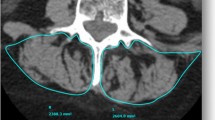

3D Muscle Reconstruction

The 3D reconstruction of individual muscles, listed in Table 1, was performed using Muscl’X software (ENSAM, Laboratory of Biomechanics, Paris, France), a validated software [9] already employed in previous literature [10]. Some muscles were combined, since the low contrast made an accurate separation of the individual muscles difficult. The lumbar part of the psoas was reconstructed separately, but at a point where the distinction with the iliacus was not possible, it was then integrated into the iliacus. The external obturator, adductor longus, brevis and magnus and pectineus were reconstructed into a single group named “Adductor.” The vastus lateralis and intermedius were reconstructed together. The muscle reconstructions were done on the fat images. Figure 1 (reprinted with permission from the authors of previous literature [10]) presents the 3D reconstruction of the left muscles for one patient. The femurs were also reconstructed on the water images; the contrast between the cortical and cancellous bones was greater on water images.

Medial and frontal view of all the left muscles reconstructed for one patient. (Reprint with permission from [10])